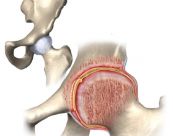

Viêm bao hoạt dịch là loại viêm các túi nhỏ (bursa) có chứa chất dịch đệm và bôi trơn các vùng giữa dây chằng và xương. Các túi bao mấu chuyển là một túi lớn phân tách các mấu chuyển lớn hơn của hông và các cơ bắp và gân của đùi và mông. Viêm bao hoạt dịch khớp háng là một chứng viêm của các túi nhỏ ở háng. Dưới đây là bài viết chi tiết về bệnh, mời các bạn tham khảo!